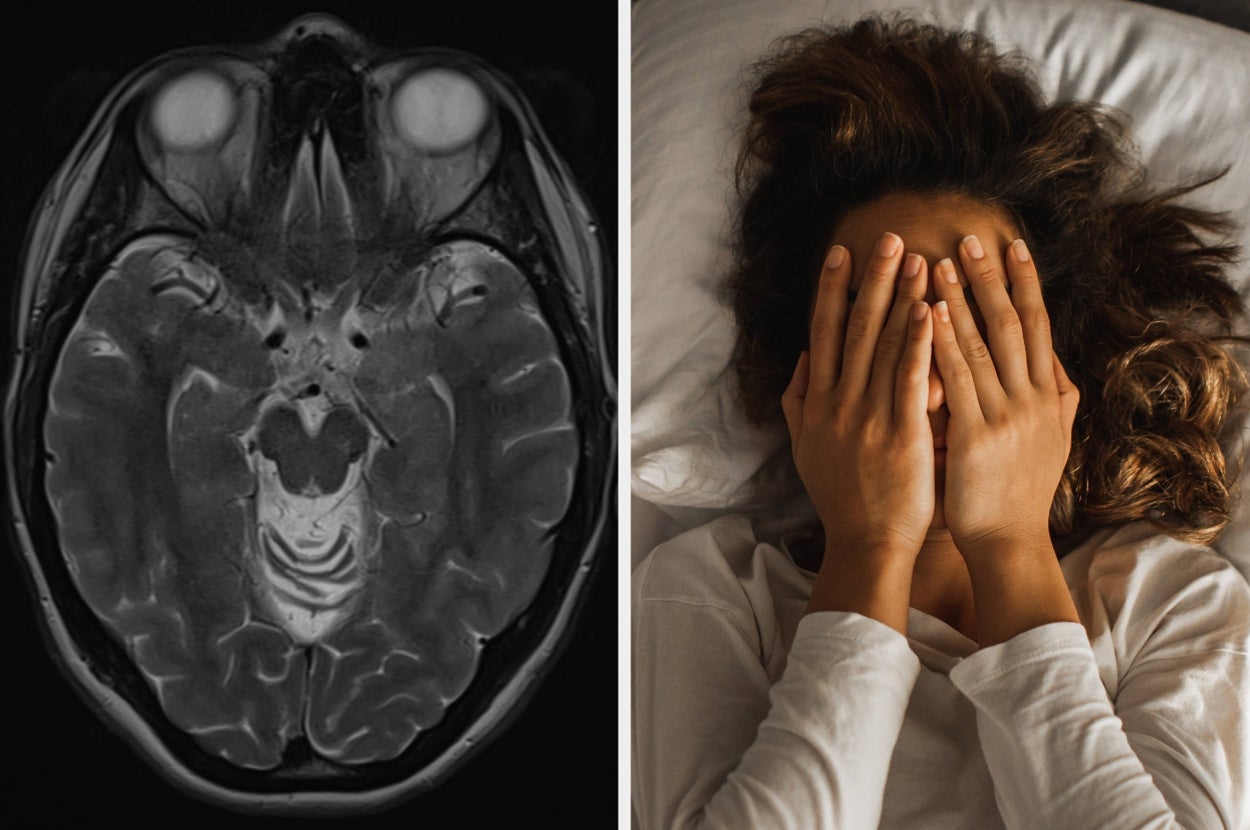

Neurologists Are Opening Up About Sleep Problems That Might Be Warning Signs Of Dementia

Experts reveal which sleep disturbances may signal something deeper, and when you should be concerned. This article originally appeared on HuffPost.